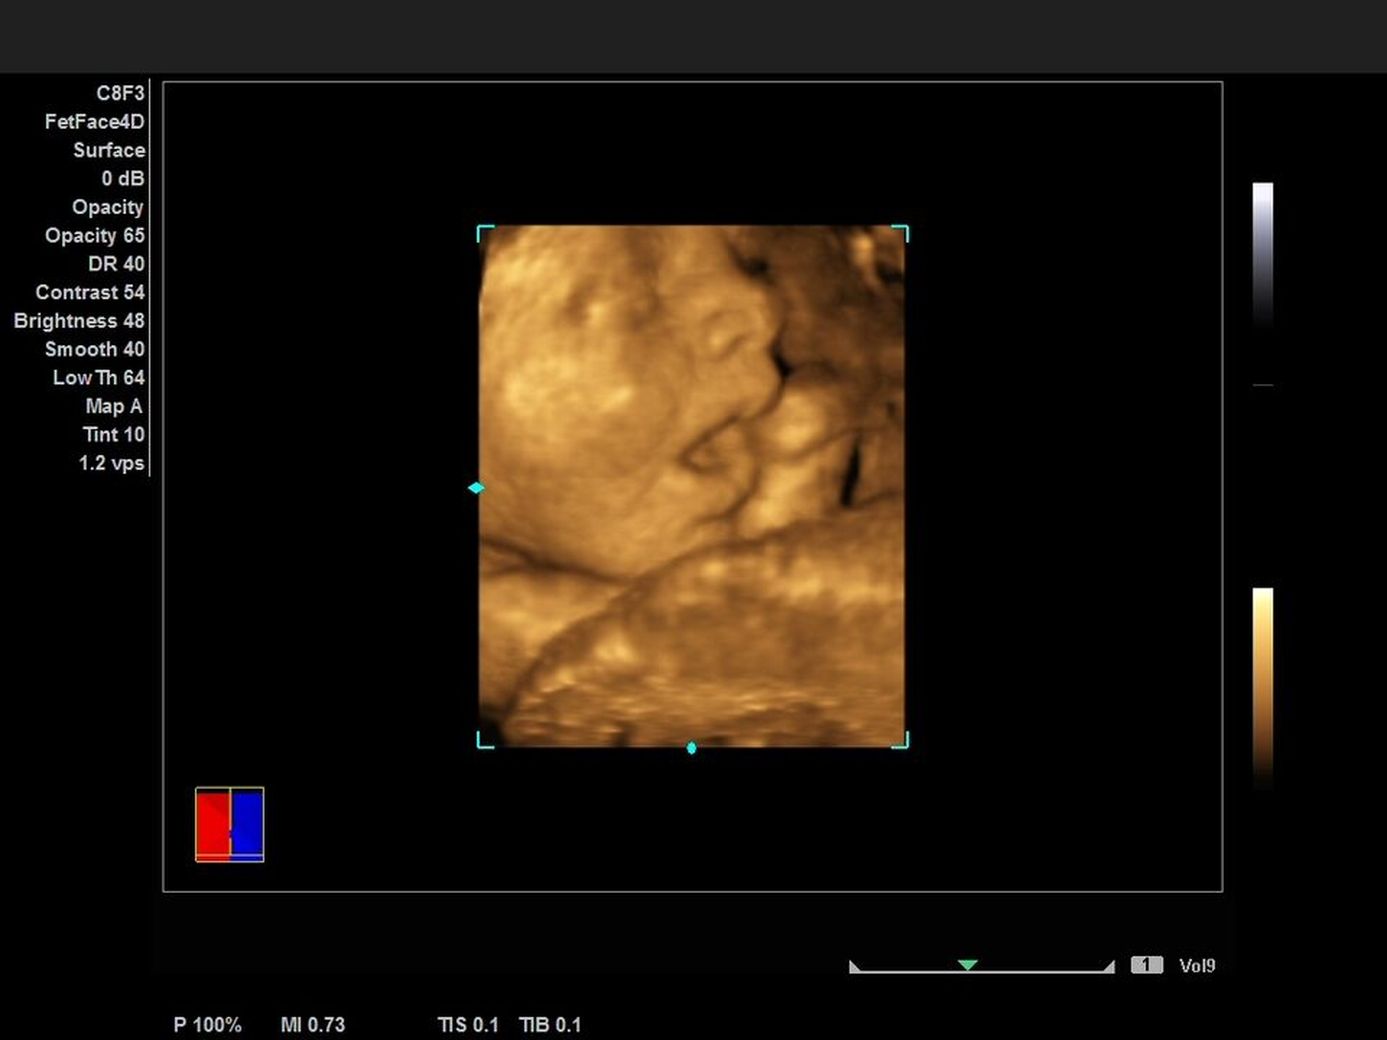

Узи 3 уровня

Узи 3 уровня 117 фотографий